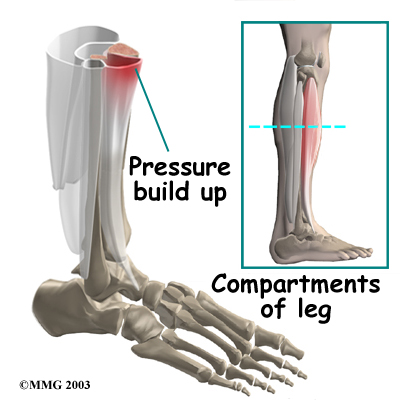

A concerning complication of shin splints is compartment syndrome. Compartment syndrome is a condition where pressure from muscle damage and swelling builds up inside a section, or compartment, within the body. There are four compartments in the lower limb. As the pressure builds in the compartment, the small blood vessels (called capillaries) that supply blood to the muscles in the compartment are squeezed shut. This happens when the pressure in the compartment is higher than the blood pressure that keeps the small blood vessels open. When the muscle loses its blood supply it begins to ache, like a muscle cramp.

If the continues to rise, it can squeeze the larger blood vessels and nerves as well. Patients may feel coldness, numbness, and swelling in the lower leg and foot. If pressure builds up and is not treated, it can cause serious tissue damage in the leg and foot.

A test for measuring pressure in the sore leg may be needed if you have symptoms of compartment syndrome. Our physical therapist checks pressures within the tissues of the leg, before and after exercise, to see if exercise causes the pressure readings to go up.